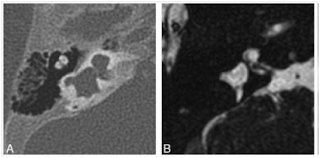

GVA SNİK'na yol açabilen en sık görülen iç kulak anomalisidir. Tek başına görülebildiği gibi IP-II, vestibüler genişleme (Vestibular Enlargement), yarım daire kanalı displazisi gibi anomaliler ile birlikte de görülebilir. BT ile 1,5 mm'den daha geniş görülmesiyle tanı konulur. Bu genişlik yaklaşık posterior YDK'nın orta yerindeki genişliğine karşılık gelir.12 MR ile endolenfatik kanal ve kese genişliklerine de rastlanılabilir (şekil 7). Endolenfatik kanal genişliği genellikle GVA ile birlikte görülse de, izole olarak da bulunabilir.

Şekil 7: A.Geniş vestibüler akuaduktus, kanalın çapı komşu YDK'dan daha geniştir. Aynı zamanda IP-II deformitesi de bulunmaktadır. B.Geniş endolenfatik kanal ve kese olgusu.

Şekil 10: A. Sağ İAK içinde ön altda kohlear sinir görülmüyor. B. Sol İAK içinde ön altda kohlear sinirin görünüşü.